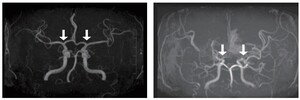

서울대학교병원 연구진이 소아 모야모야병의 조기 진단을 가능하게 하는 새로운 바이오마커를 발견했습니다. 이 발견은 조기 치료와 관리에 중요한 역할을 할 것으로 기대됩니다....